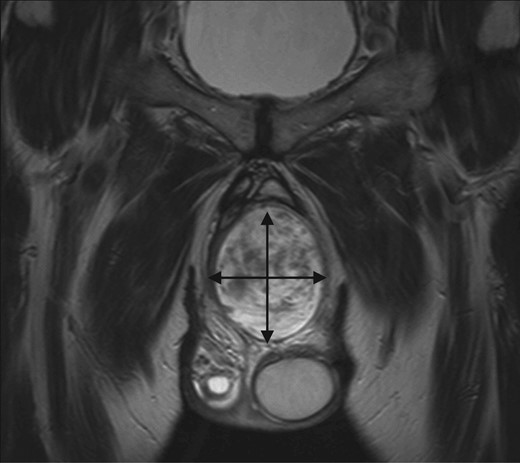

An initial ultrasound confirmed a well-defined heterogenous encapsulated solid mass with internal vascularity. An abdominopelvic MRI revealed a 5.4 cm × 7.2 cm × 15.7 cm solid-cystic well-defined lobulated mass within the perineum separate from the testicles, adjacent to the penis and extending to the right ischial fossa and the obturator internus muscle (Fig. 1). Anteriorly the mass displaced the penile urethra and bulb and the anal sphincters without direct involvement (Fig. 2). There was no locoregional or para-aortic lymphadenopathy.

MRI abdomen and pelvis T2 weighted sequence coronal view demonstrating well-defined heterogeneous mass within the perineum.